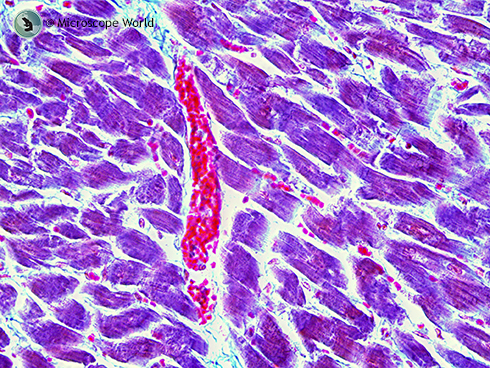

Human Cardiac Muscle under Microscope

Human cardiac muscle captured under the RB30 microscope at 100x magnification with a 5mp microscope camera.